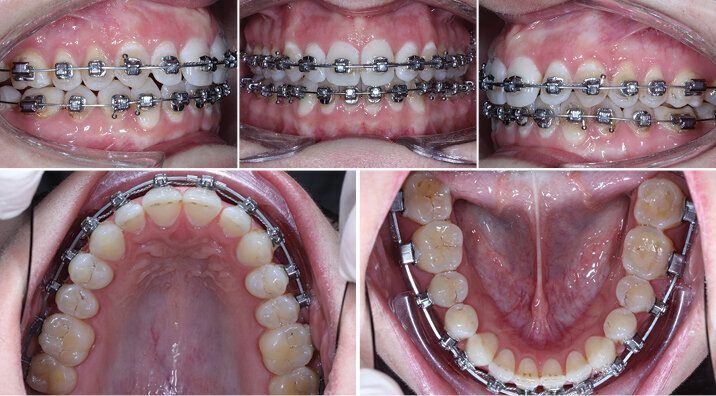

Dospělá žena, mezocefalická, skeletální I. třída, otevřený skus. Pacientka trpěla častými bolestmi hlavy.

Uzavřít otevřený skus a zachovat vertikální pozici horních řezáků.

Použitý aparát: Insignia SL – individuální vestibulární Damon zámky

Vstupní intraorální fotografie